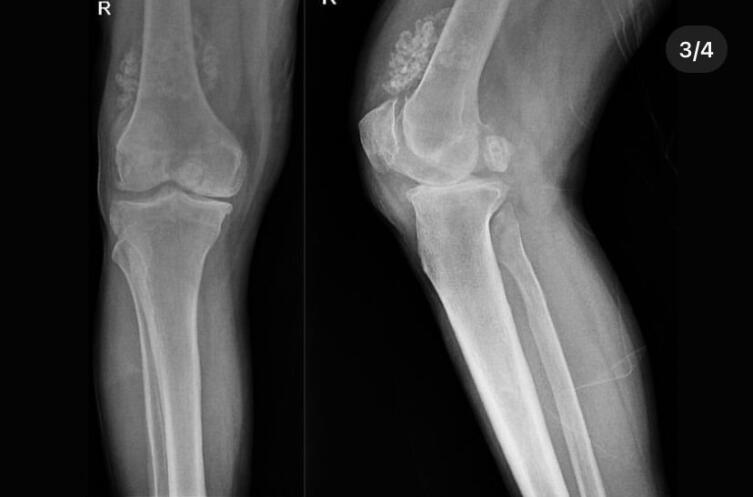

Türkiyənin Düzcə şəhərində bir xəstənin dizindən cərrahi yolla 41 "oynaq siçanı" (qığırdaq və ya sümük quruluşunun pozulması nəticəsində qırılan parçalar) çıxarılıb.

Müayinələr zamanı xüsusilə xəstənin diz oynağının ətrafında 41 "çox sinovial xondromatoz" halı aşkar edilib. Düzcə Universiteti Tibb Xəstəxanasında endoskopik üsulla edilən əməliyyatla xəstənin dizindən sözügedən hissələr çıxarılıb.

Dos. Dr. Zekeriya Okan Karaduman, Dos. Dr. Mehmet Arıcan və Dr. Müəllim Üzv Sönmez Sağlamın çıxardığı parçaların ölçülərinin bir neçə millimetr ilə santimetr arasında dəyişdiyi bildirilib.